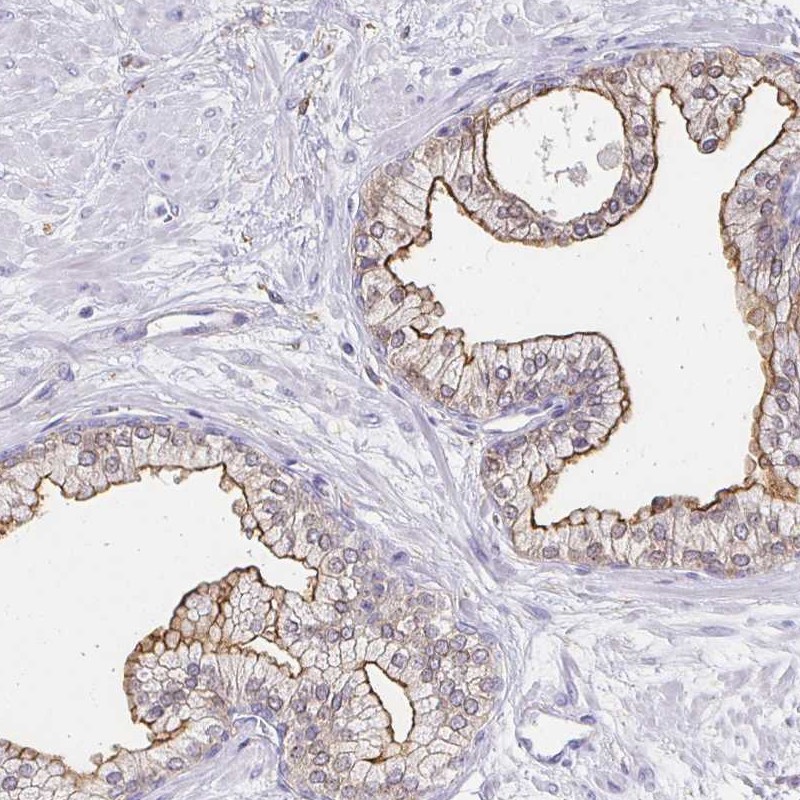

Immunohistochemical staining of human prostate shows moderate membranous positivity in glandular cells.